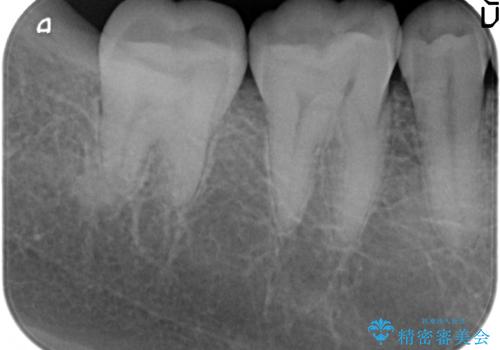

- 右下の一番奥の歯で冷たいものを飲むとしみるので診て欲しいといらっしゃった方の症例です。

ついでに銀歯もやり替えたいとのことだったので、右下6、7番目の歯に対してセラミックインレーによる修復を行いました。